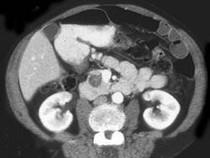

患者,女,57岁,上腹部隐痛半年余,CT片,最可能的诊断是 ( )A.胰腺癌B.胰腺脓肿C.胰腺假性囊肿D.胰腺囊腺瘤E.胰岛细胞瘤

问题 患者,女,57岁,上腹部隐痛半年余,CT片,最可能的诊断是 ( )

选项 A.胰腺癌 B.胰腺脓肿 C.胰腺假性囊肿 D.胰腺囊腺瘤 E.胰岛细胞瘤

答案 D